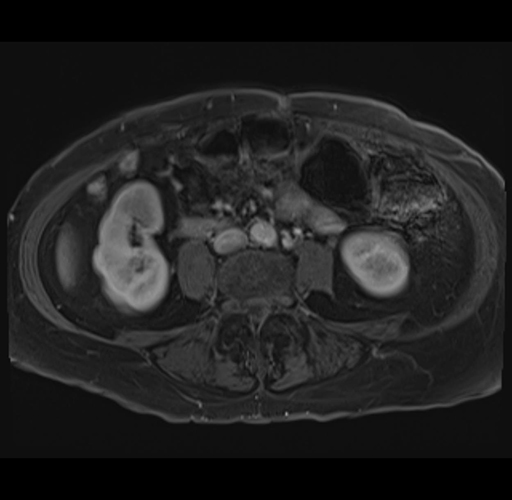

MRI T1